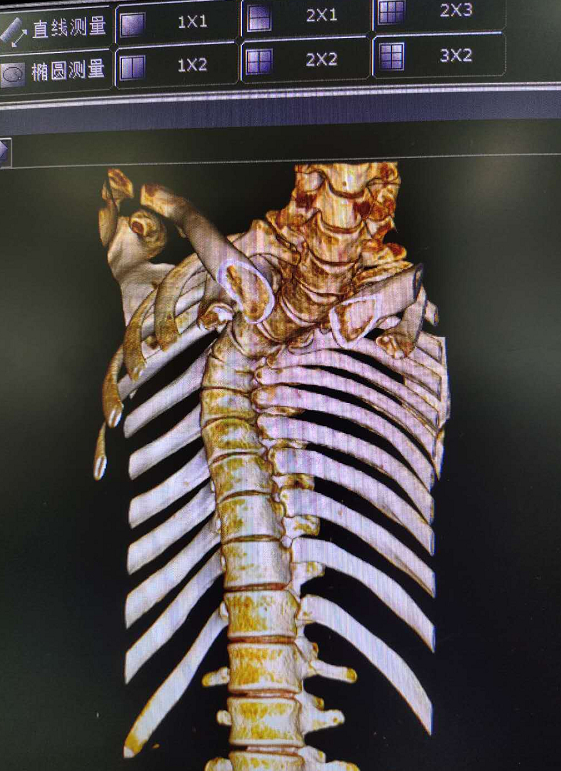

7月底,已经大学毕业的张强在老师的帮助下,被爱心组织送到了贵航三〇〇医院接受治疗。彭医生告诉记者,一般特发性脊柱侧弯小于20度,可以通过注意姿势和针对性锻炼进行矫正,而张强的脊柱后凸侧弯畸形严重,已经大于50度,心肺因受压迫导致心肺功能明显降低,属于极重度脊柱侧弯。手术有瘫痪、大出血,术后感染等风险,手术难度非常大。

彭建兴主任医师带领医疗组进行了充分的术前准备,并进行了全院会诊。经过6个多小时的手术,张强弯曲的脊柱得以矫正恢复。彭医生说,张强的术后恢复愈合非常好,神经功能、呼吸功能都比以前顺畅多了,还可以增高4~5公分。最主要是矫型之后,脊椎不受压了,心肺功能不受影响。